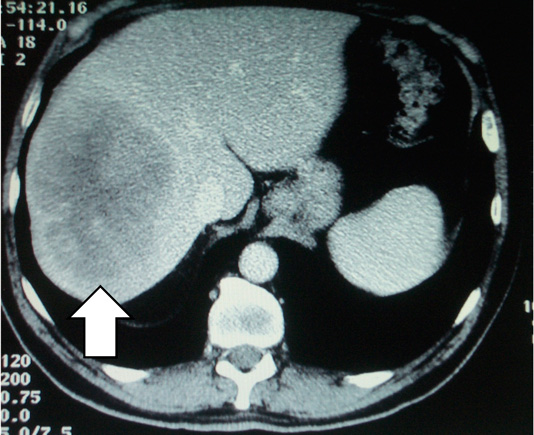

These CT scans show a secondary deposit in the liver from a cancer of the colon, before chemotherapy (left) and after chemotherapy (right). The patient then underwent surgery, but the significant shrinkage made for a lesser operation.